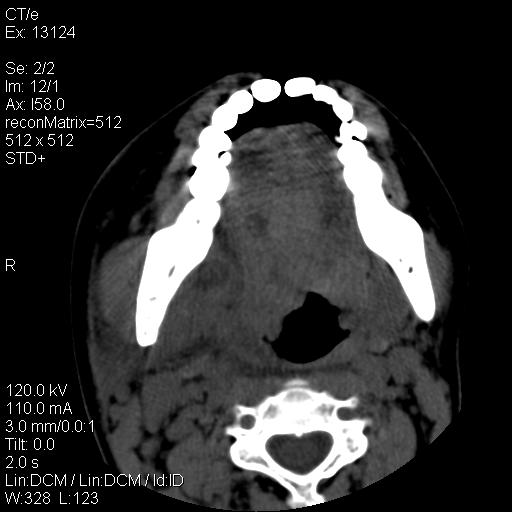

女,29岁,右下磨牙痛,因产后2月,故未治疗。现右颌肿痛伴张口困难。请大家看看右侧鼻咽部、口咽部是否

1.考虑右侧下颌区脓肿(牙源性)

考虑右下智齿冠周炎伴周围软组织炎症,脓肿形成

1)考虑右侧下颌区软组织脓肿(牙源性)。2)鼻咽部炎性改变;建议追踪复查。3)右侧上颌窦炎。4)双侧下鼻甲黏膜肥厚。

1)考虑右侧下颌区牙源性软组织脓肿。2)右侧上颌窦炎。3)双侧下鼻甲黏膜肥厚。4)鼻咽部炎性改变;建议追踪复查。

考虑右下智齿冠周炎伴周围软组织脓肿形成。